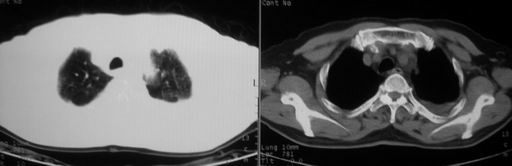

男,78岁,咳嗽、咳痰、发热入院,抗炎治疗一周后已退热,咳血似痰。

10月3日片:

ct左肺下叶大片状高密度影,病变密度不均,界限不清,左侧胸腔积液,治疗后复查临床症状好转而影像学表现病变有发展,还是首先考虑感染性病变,复查时间短附合感染性病变的病理改变。

两肺炎症感染(以左肺下叶为著),双侧少量胸腔积液;建议继续抗炎治疗。